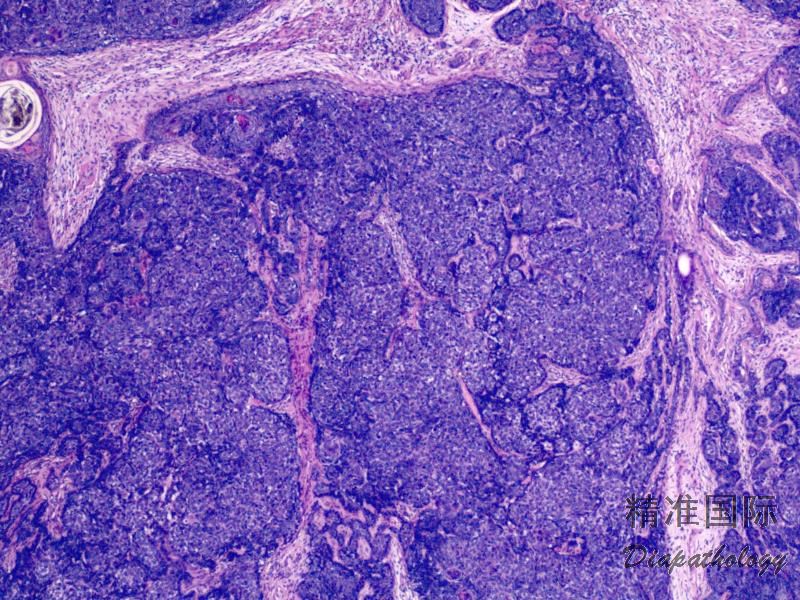

肿瘤位于真皮或皮下组织, 对称性生长,边界清;

镜下见基底样细胞排列成索状、板状或簇状,周围细胞核呈栅栏状排列;

细胞巢团周围有纤维基质增生,无基底细胞癌的细胞巢与间质间的裂隙;

可见毛乳头体。